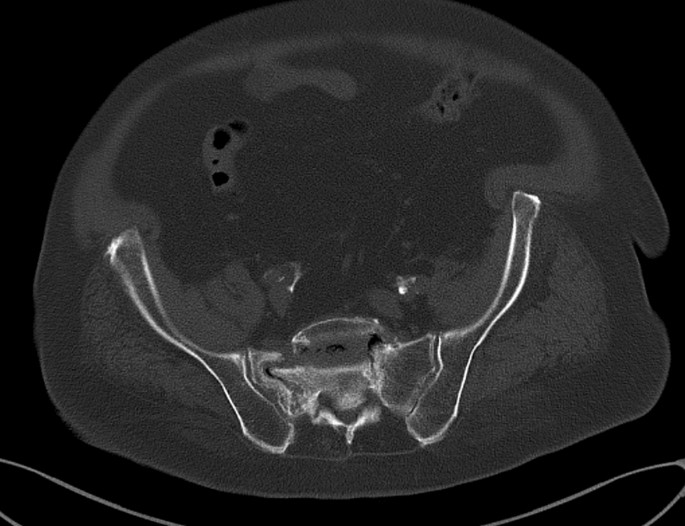

As the indications for surgical treatment of FFP proposed by Rommens and Hofmann were type IV of FFP and inability to walk weight-bearing4, the studied sample, included patients over 65 years old diagnosed with osteoporotic FFP type IV who were unable to walk weight-bearing.

In the operating room, the patient was in a prone position (Fig. 1). Using the C arm (Cios Fusion Siemens, Germany), the level of the sacral bone was evaluated. The plates were applied using the Krappinger modified method as presented in Figs. 2 and 315. Two longitudinal incisions were made laterally from the sacroiliac joints. Next, a chisel was used to prepare a subfascial tunnel towards the opposite side, and grooves in the iliac spine were made. After bending, the locking compression plate was slid to the opposite side and after turning 180° fixed with 3.5 mm screws. The first screw was applied in a sacral bone just medially to the iliosacral joint in order to fix the plate to the bone. These screws were approximately 3–4 cm long and oriented in a sagittal axis. They were supposed to run laterally to the sacral foramina. The additional 2–3 screws on each side were inserted in the ilium, laterally to the iliosacral joint. These screws were applied about 30 degrees to the sagittal plane not to penetrate the sacral foramina and were 2–3 cm long. Two ilioiliac plates (3.5 mm system DePuy Synthes) were applied as presented in Fig. 4. The first was at the level of S1, and the second was at the level of S3. The anterior ring was not stabilised so as not to exceed the operation time and not to turn the patient over. According to former literature, we assumed fixing the posterior ring with two plates to be stable enough10,11,12,16.